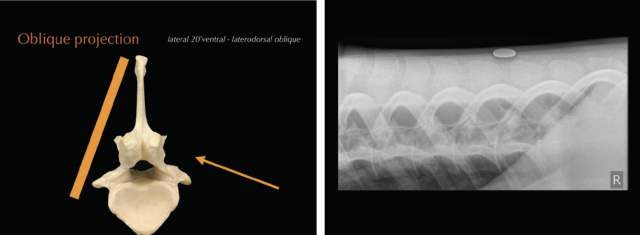

• Radiography allows the visualisation of the vertebral column, intervertebral articulations (IVAs/’facet joints’) and vertebral bodies to a varying degree, depending on location, equipment and patient size. Latero-lateral views as well as oblique projections can be obtained. Standard radiographs ideally include three to five overlapping latero-lateral radiographs using radiopaque markers, such as coins, for orientation. Collimated views of specific regions of interest can help to increase image quality by reducing scatter. Main limitations of the technique include attenuation and inability to visualise lumbar vertebral bodies. Care should be taken when interpreting or measuring interspinous spaces (ISS). Geometric distortion markedly affects the appearance of the spaces, depending on the shape and the distance of the dorsal spinous processes to the focal spot emitting X-ray beams (Djernæs et al 2017). Furthermore, the head position influences the distance between thoracic dorsal spinous processes and it is therefore advised to acquire back radiographs in a neutral position with the muzzle at shoulder level (Berner et al 2012). To further assess intervertebral articulations, oblique projections are obtained with the beam angled 20˚ from ventral to dorsal and centred 15-20cm ventral to dorsal midline (Butler et al. 2000; Girodroux et al. 2009). The X-ray plate should be aligned perpendicular to the beam and as close as possible to the horse. The highly-curved shape of the ribs is causing superimpositions with to the thoracic IVAs. In the lumbar spine there is superimposition of the transverse processes and abdominal structures.